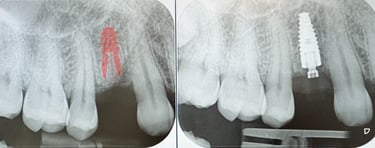

Yleensä aina ensisijainen vaihtoehto on että implantti asetetaan paikoilleen samassa toimenpiteessä kun hammas poistetaan. Tekniikat ja materiaalit on kehittyneet niin että enää ei tarvitse odottaa luun paranemista ennen implantointia. Jos hammas on jo poistettu niin 6-8vk kohdalla voidaan implantti asettaa tässä tilanteessa.

Hammasimplantti on titaaninen tai keraaminen 'ruuvi' joka asetetaan luuhun. Tämän varaan voidaan valmistaa yksilöllinen hammas.